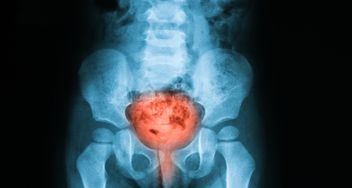

Radiografia Del Cuerpo Humano Y El Esqueleto Con Dolor En Las Piernas Fotos Retratos Imagenes Y Fotografia De Archivo Libres De Derecho Image 23789245